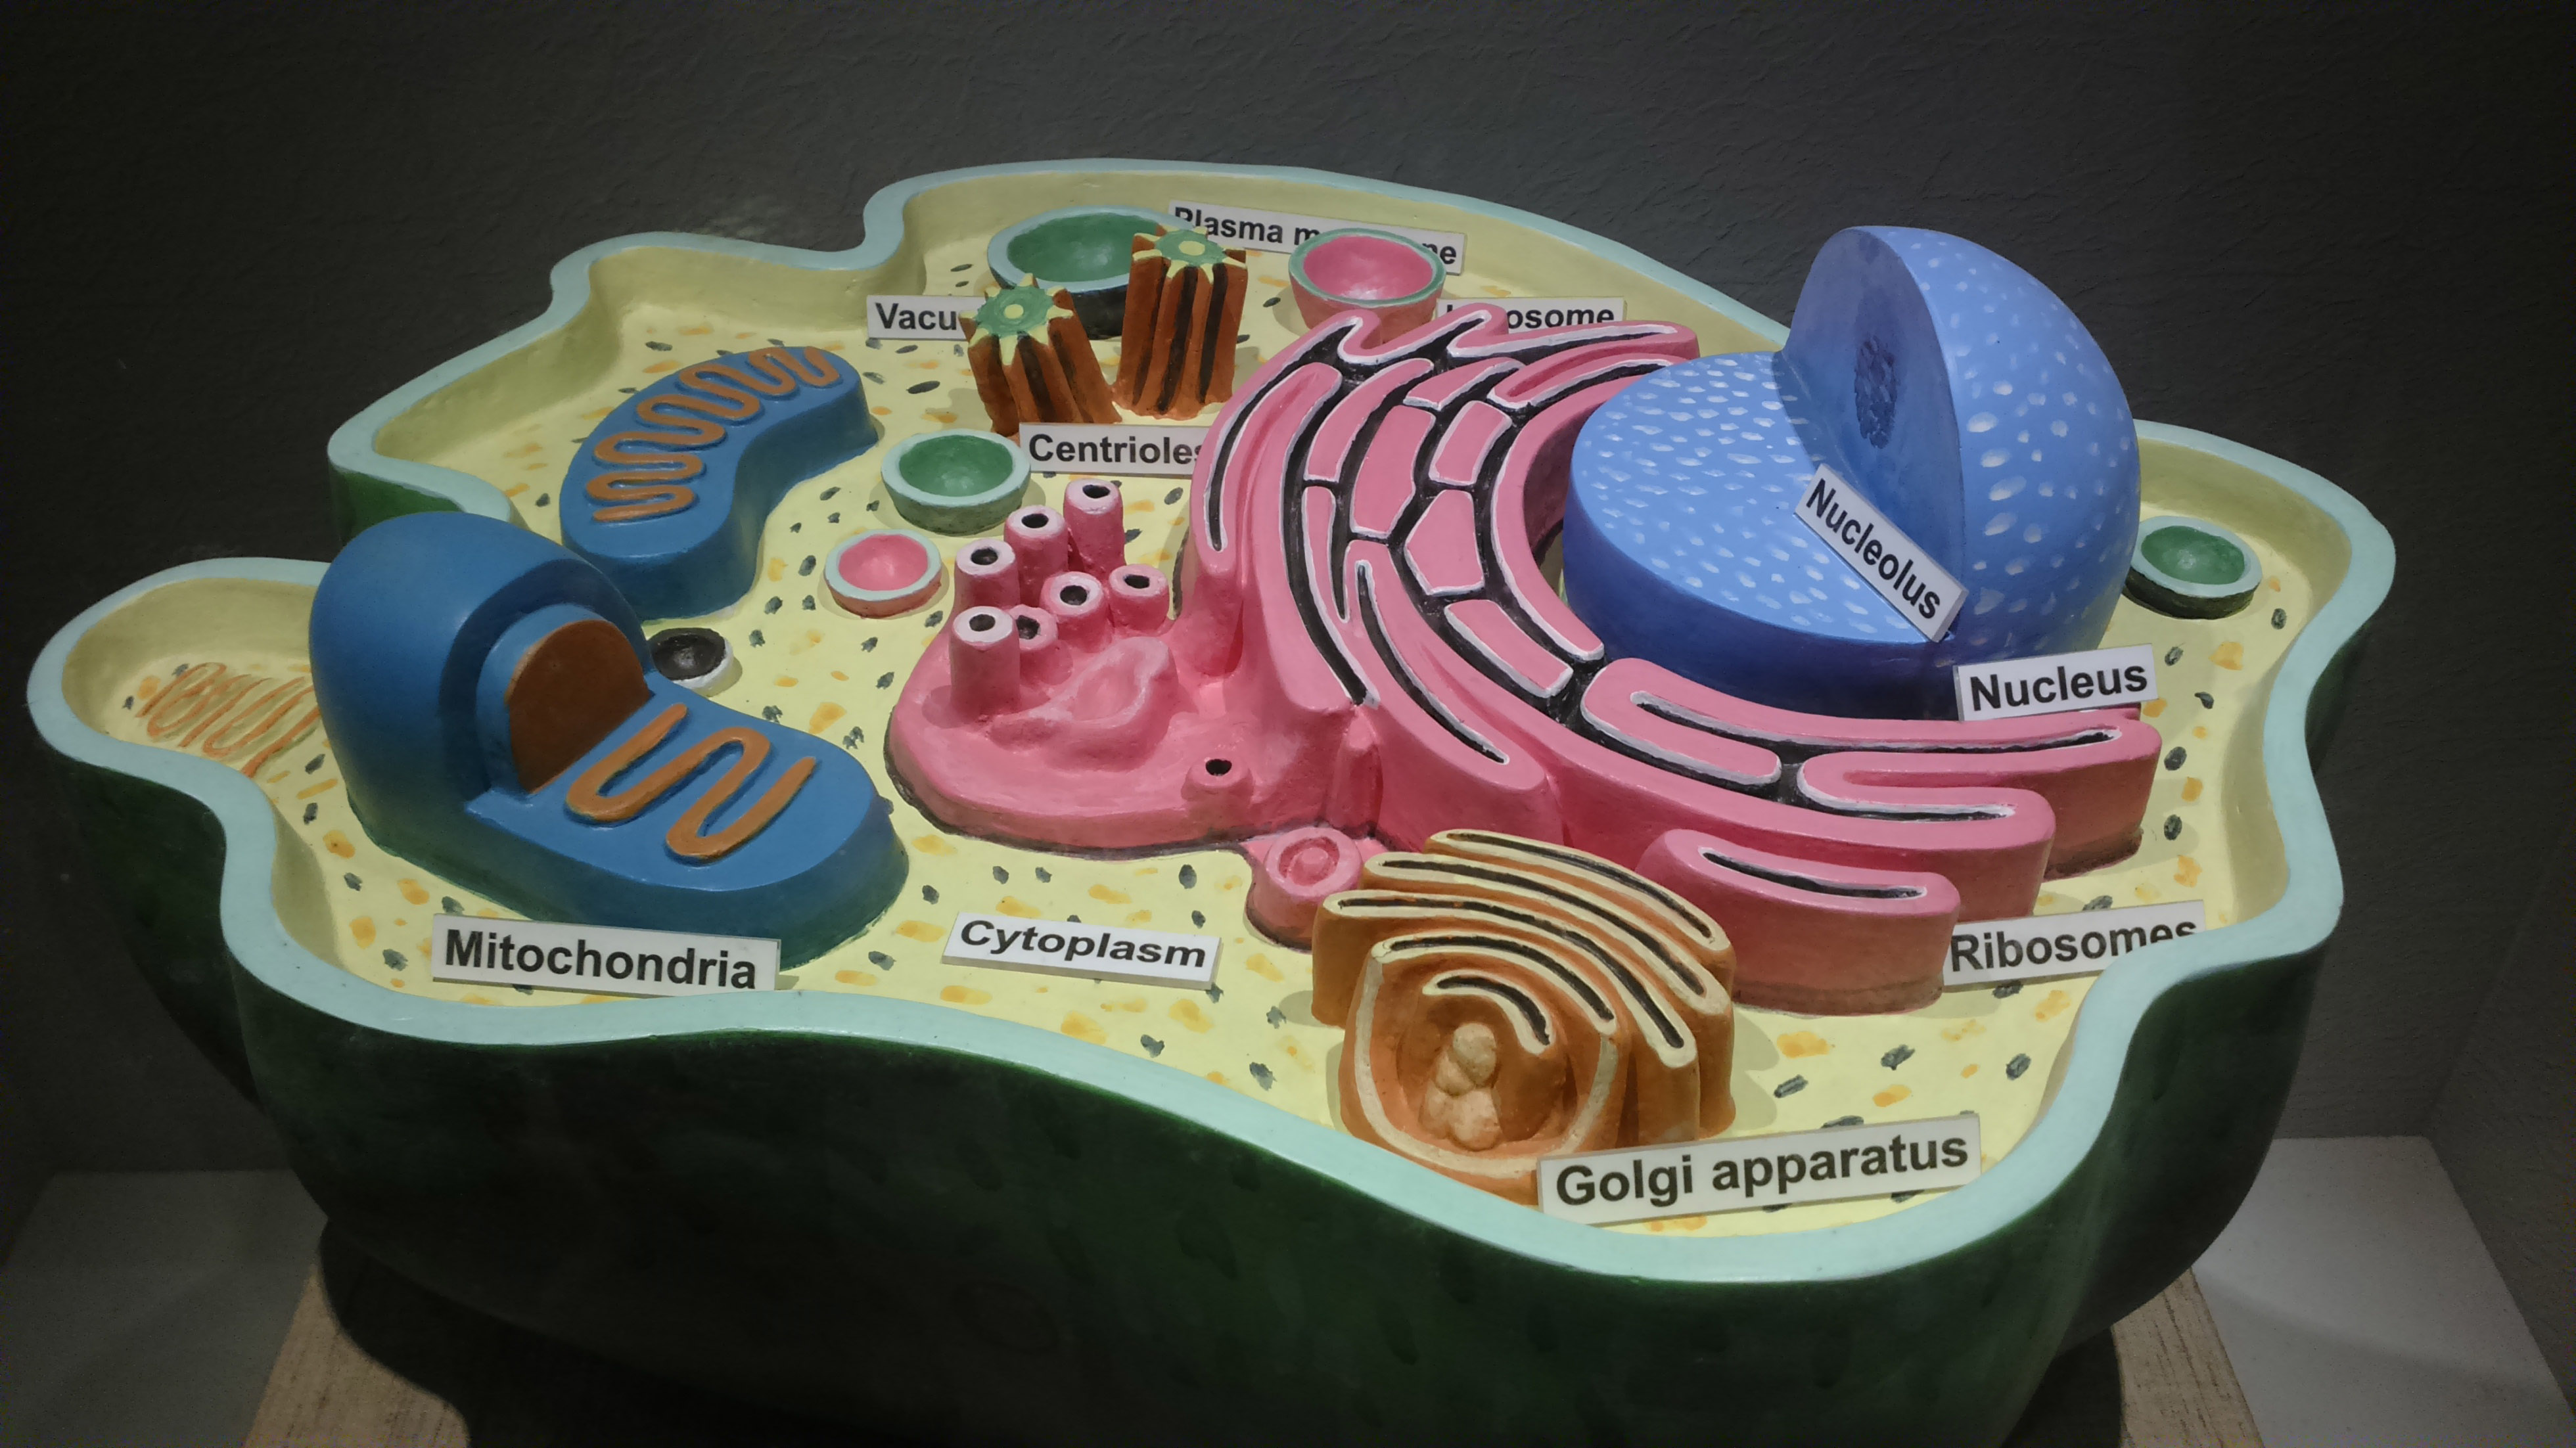

قیمت: 58٬000 تومان - دسته بندی فایل: علوم پزشکیپاورپوینت فیزیولوژی سلول

فروش ویژه پاور پوینت حرفه ای فیزیولوژی سلول با تخفیف استثنایی فقط 82 هزار تومان تعداد اسلاید: 50 اسلاید